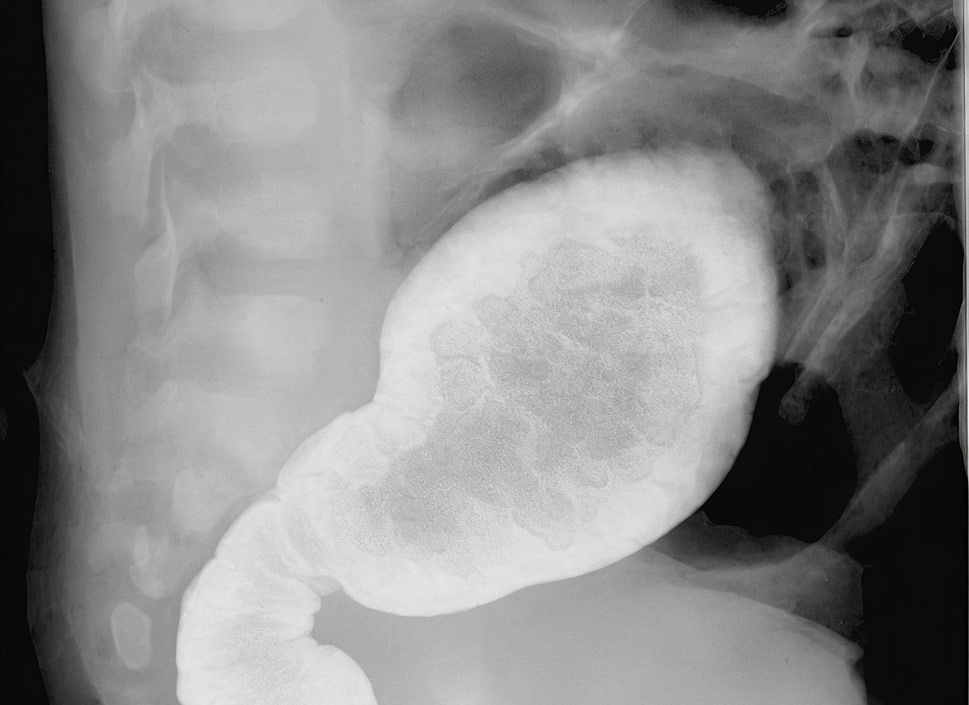

El enema de bario doble contraste se ha convertido en un procedimiento estándar para evaluar la salud de tu colon. Este examen utiliza un medio de contraste, conocido como bario, que mejora la visualización de las estructuras internas.

Este procedimiento involucra la introducción de bario en el colon, seguido de aire para expandirlo, permitiendo una mejor visualización de las paredes intestinales durante la radiografía.